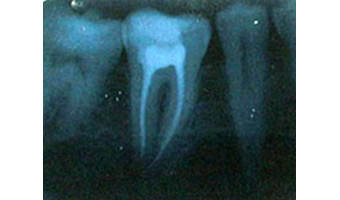

Lower right first molar (centre) after root canal therapy;

the pulp chamber and root canals have been cleaned

of debris, decontaminated and filled with gutta percha.

• The canals inside the tooth are cleaned, sterilized then filled to seal them from future infection. The standard filling material is gutta-percha, a natural thermoplastic polymer of isoprene.